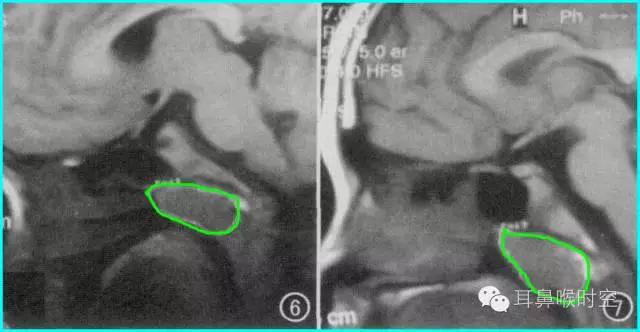

久而久之会影响宝宝颜面部的发育,使本来很漂亮的五官逐渐变丑,宝宝的上牙会向外突出,上嘴唇也向外翘起,使宝宝看起来比较呆傻,也就是通常所说的“腺样体面容”。